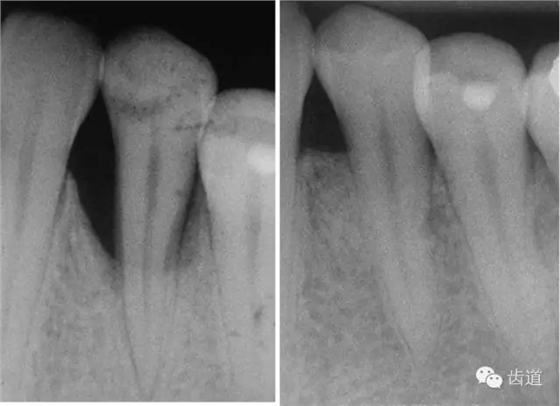

1、垂直型骨缺損:垂直性吸收形成的骨下袋,三壁袋和二壁袋的效果好,一壁袋的效果最差;

2、根分叉病變:II度或III度根分叉病損,II度效果最好;

如術(shù)區(qū)患牙無咬合創(chuàng)傷;為垂直性骨吸收且在III度以內(nèi);殘留骨壁數(shù)目多(三壁骨下袋);骨缺損窄而深(角度<250°,深度>3mm);牙齦組織較寬且厚度>1mm(抗張強(qiáng)度大及血供充分)時(shí);則臨床附著水平和骨量增加顯著。另外,根據(jù)病損牙位的特征(前牙、后牙、鄰間隙、根分叉等)選擇不同形狀、大小的屏障膜也很重要。

一般而言,不可吸收性膜的硬度較可吸收性膜高,其支架作用更強(qiáng)。因此在較寬的病損區(qū)(X線顯示角度大)或缺乏解剖結(jié)構(gòu)支持(如二壁骨缺損)時(shí),可選用不可吸收性膜;對于窄而且有支持的病損區(qū)(如三壁骨缺損),則應(yīng)用可吸收性膜更為有利。雖然各種膜材料的臨床療效無明顯差別,但如果聯(lián)合應(yīng)用植骨材料時(shí),選用可吸收性膜則僅需一次手術(shù),損傷小,操作也便利。